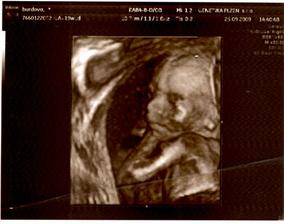

berija

13. bře 2009

Nelinka -tak jde čas🙂